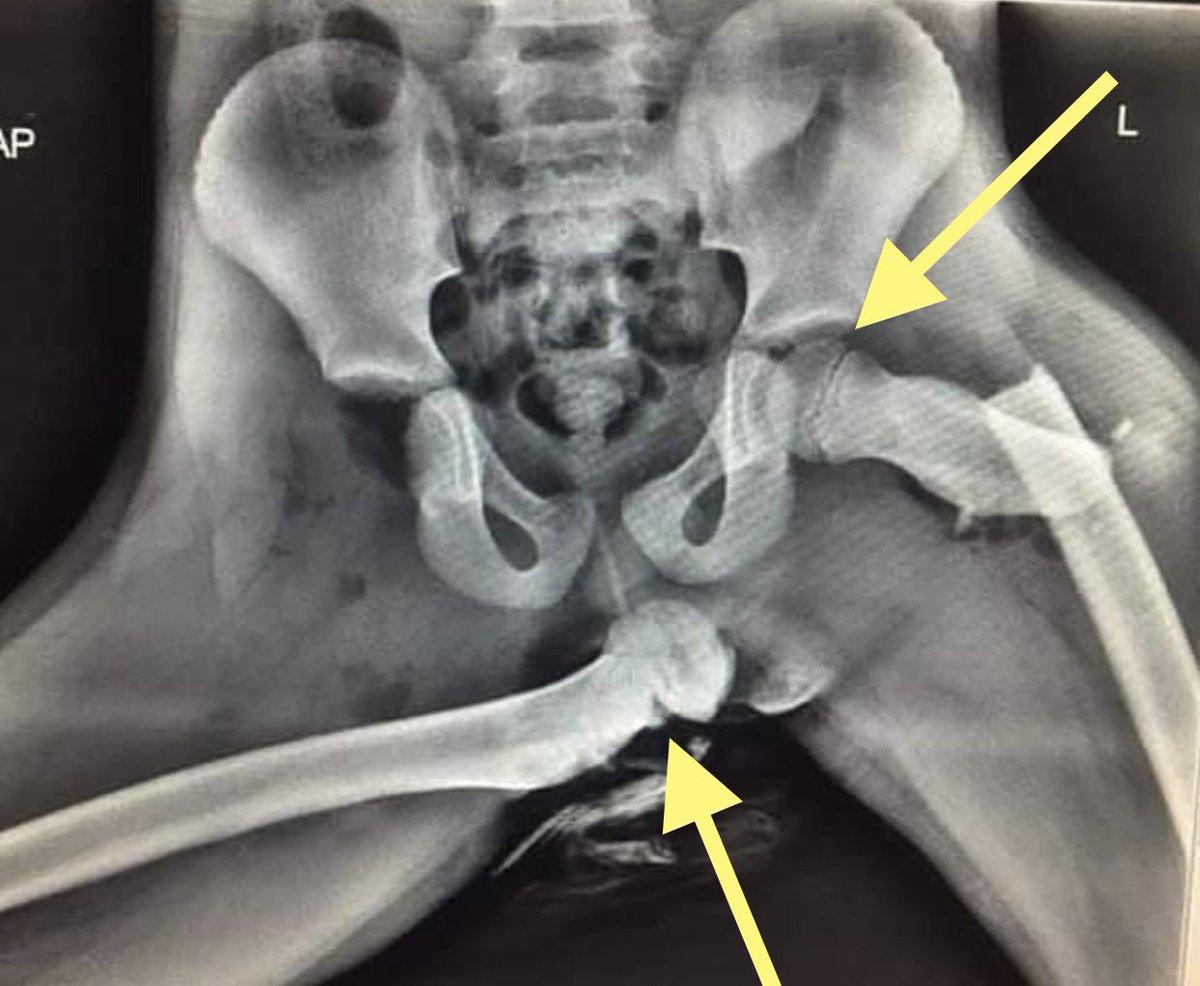

Exemple (il y en a des dizaines, avec cette radiographie)

"Une femme se fracture les hanches (bla bla) tableau de bord... (bla bla)"

"Horrifying X-ray shows why you should not put your feet on car dashboards"

"Bad car habit you need to stop"

Vous remarquerez si vous cherchez que c& #39;est toujours la meme image, celle-ci  https://abs.twimg.com/emoji/v2/... draggable="false" alt="👇" title="Rückhand Zeigefinger nach unten" aria-label="Emoji: Rückhand Zeigefinger nach unten">

Or cette radio n& #39;est pas celle d& #39;une femme...

Or cette radio n& #39;est pas celle d& #39;une femme...

Mais celle d& #39;un enfant... comme on peut le voir ici (fléchés) car les cartilages de croissance des fémurs ne sont pas soudés (le trait noir entre l& #39;epiphyse et la métaphyse) contrairement à une hanche adulte.

(Il y a d& #39;autres signes en faveur d& #39;un enfant)

(Il y a d& #39;autres signes en faveur d& #39;un enfant)